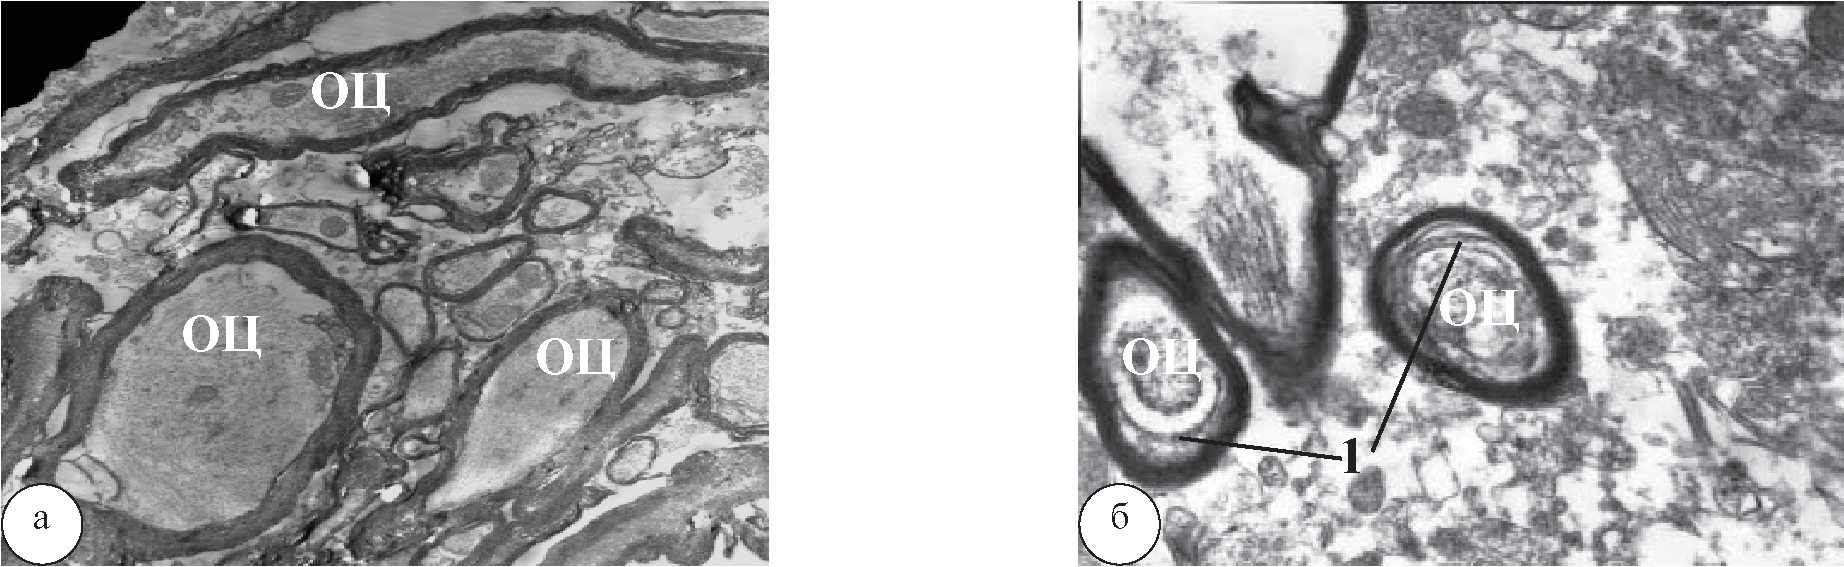

МВ у крыс КГ после КИН через 1 месяц были полиморфными. В резко измененных МВ отмечалось набухание миелиновых ламелл с потерей их четкости и расслоением как по всей толще миелина, так и периаксонально; встречались истончения и разрывы ламелл. Осевые цилиндры (ОЦ) нервных волокон были прозрачны либо умеренно осмиофильны вследствие их сжатия. «Толстые» МВ имели выраженные признаки аксонопатии, а иногда их ОЦ состояли из двух частей: очень плотной и почти прозрачной с измененными ми- тохондриями, окруженными обрывками миелина. ОЦ безмиелиновых волокон (БМВ) почти всегда были обеднены органеллами частично или полностью (рис. 3а).

Через 1 месяц лечения с помощью ТКМС миелинопатия в МВ была умеренной и проявлялась лишь набуханием и расслоением ламелл. ОЦ имели обычную плотность и содержали несколько повышенное количество митохондрий с плотными кристами. В большинстве БМВ (как и в МВ) ОЦ также были почти полностью сохранными, а вокруг МВ эндоневрий имел обычный вид (рис. 3б).

Рис. 3. Участок СМ крыс после КИН в области поясничного утолщения: а – МВ крыс КГ. Наблюдаются умеренные изменения ОЦ и выраженная миелинопатия (А), ув. ×20000; б – МВ крыс после лечения с помощью ТКМС. Наблюдаются умеренная миелинопатия в виде набухания миелина (1) и почти сохранный ОЦ, содержащий плотные митохондрии, ув. ×16000.